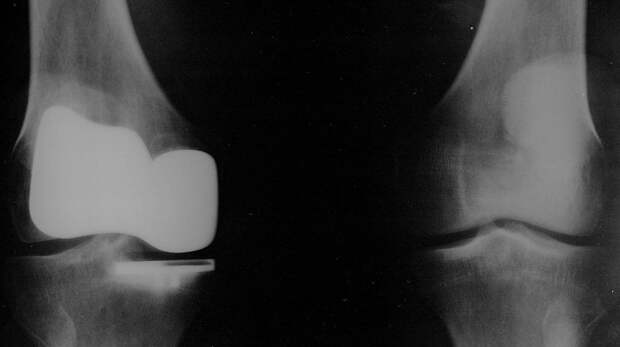

Прототип биосовместимого имплантат для коленного сустава разработали молодые ученые из НИТУ МИСИС, 22 июня сообщает пресс-служба университета. «Прототип биосовместимого костно-хрящевого имплантата коленного сустава разработали молодые ученые НИТУ МИСИС», — говорится в сообщении. Предполагается, что создаваемые изделия выйдут на российский рынок.

Для замещения хрящевой ткани использовался термопластичный полиуретан, заполненный сфероидами из хондроцитов — клеток хрящевой ткани, для замещения костной ткани — полилактид с гидроксиапатитом, заполненный сфероидами из осеобластов — клеток костной ткани. Как подчеркнула автор разработки магистрантка МИСИС Анна Дианова, используемые материалы не оказывают на клетки токсическое воздействие. Отмечается, что в разработке используется биосовместимые материалы и тканевые сфероиды. Это обеспечивает приживаемость и повышает регенерацию ткани. Сообщается, что заболевание коленного сустава является распространенной причиной инвалидности среди старшего поколения. По данным отечественной статистики около 4,5 млн граждан страдает от данных заболеваний, в реальности число может достигать 15 млн. Причиной называется не вылеченные вовремя повреждения, так как хрящевая ткань имеет низкий уровень регенерации, это может привести к замене коленного сустава. Подчеркивается, что в планах получение патента и доклинические исследования, разработкой заинтересовались в Минздраве РФ. Напомним, что в марте 2021 года в РФ заявляли об испытаниях препарата по восстановлению хряща коленного сустава. В январе 2020 года в Китае сообщалось о проведении роботом операции по замене тазобедренного сустава человеку. В декабре 2022 года заявлялось, что полностью разработанный в Китае хирургический робот провел операцию по замене человеку коленного сустава. Читайте также: Китайский робот провел первую операцию по замене коленного сустава человека Читайте также: Китайский робот провел операцию по замене тазобедренного сустава Читайте также: В РФ начнут испытания препарата, восстанавливающего хрящ коленного сустава